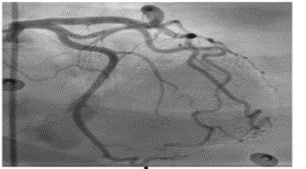

Critical violations ECG and coronary readings EChOKG changes

1 Acute coronary syndrome with

ST-segment elevation and coronary

syndrome without ST-segment elevation

2 Acute myocardial injury without vascular atherosclerosis